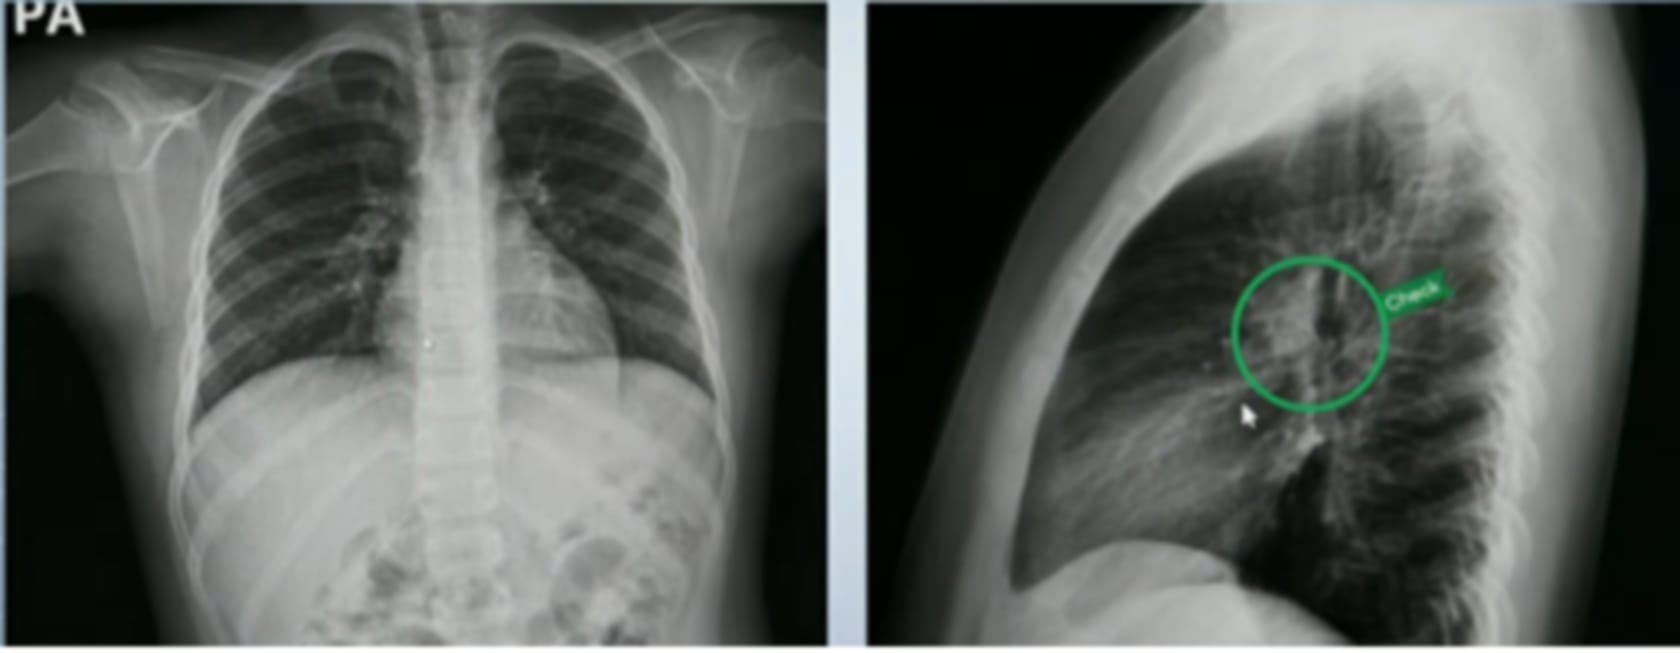

급성 기관지염은 주로 임상 증상과 병력 청취를 통해 진단한다. 가장 특징적인 증상은 2~3주 이상 지속되는 기침이며, 청진 시 천명음이나 수포음이 들릴 수 있다. 흉부 방사선 촬영은 폐렴이나 다른 하부 호흡기 질환과의 감별을 위해 필요할 수 있으나, 모든 환아에서 반드시 시행되지는 않는다. 바이러스 원인을 확인하기 위해 인플루엔자, RSV, 백일해 등의 진단 검사가 시행되기도 하며, 혈액검사는 일반적으로 진단에 큰 도움이 되지 않는다. 기침이 8주 이상 지속되거나 증상이 악화되는 경우에는 다른 호흡기 질환 여부를 배제하기 위해 추가적인 검사가 필요하다.